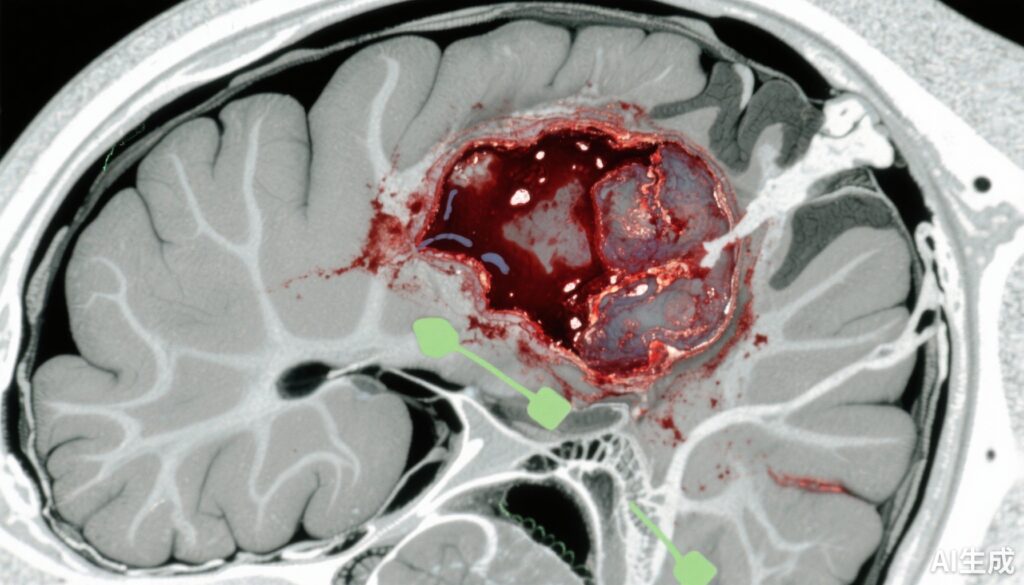

创伤性脑损伤(TBI)仍然是全球致病和致死的主要原因之一,急性硬膜下血肿(ASDH)是其中最严重的颅内病变之一。ASDH是由硬脑膜与脑表面之间的出血引起的,通常由于头部创伤导致颅内压升高和潜在的脑疝。传统的治疗方法是紧急手术清除以减少占位效应和继发性脑损伤。然而,由于损伤严重程度和患者因素的异质性,许多情况下立即手术是否优于保守治疗仍存在不确定性。这种不确定性导致了临床实践中的变异,并突显了需要明确最佳治疗策略,以平衡ASDH管理的风险和收益。

在2697名入组患者中,711名(平均年龄46.5岁,76%为男性)符合ASDH的标准。其中,148名(21%)接受了急性颅骨手术,而563名(79%)接受了初始保守治疗。

基线差异显示,手术组的病情更重:他们的格拉斯哥昏迷评分(GCS)较低(平均6.8 vs 11.4),双侧无反应瞳孔的发生率较高(32% vs 9%),并发颅内病变的比例更高(69% vs 53%)。在手术组中,87%进行了减压颅骨切除术,11%进行了开颅术。在接受保守治疗的患者中,12%最终需要延迟手术。